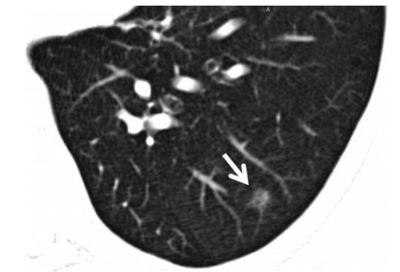

肺部结节是什么?对人体有严重危害吗?随着医学影像技术进步:高分辨率CT普及后,肺结节检出率显著提高,部分健康人(尤其是40岁以上)在体检中可能偶然发现肺结节。就是这些结节,让大家感到困惑,为什么会有结节,这些结节是什么,有什么危害,带着这些疑惑,今天俞医生就给大家来讲一讲关于肺结节的事情。 肺部结节是什么...

肺结节随访复查有黄金时间点?错过真会误大事?必看!你有没有过这样的经历,体检发现肺结节后,瞬间感觉头上像悬了一把剑。医生让定期随访复查,但具体什么时候去复查,你完全摸不着头脑,心里一直犯嘀咕,生怕错过什么关键时间点,导致病情恶化。这迷茫的感觉,就像在黑暗中走路,找不到方向。 那么问题来了,肺结节随访复查的黄金时间点...

咱国家的 AI 辅助诊断工具进了基层医院,肺部结节误诊率降了 30%!旁边弹出一行字:“考虑良性结节,建议随访”。“这玩意儿是真顶用啊。” 王医生嘴里嘟囔着,顺手端起桌边的搪瓷杯喝了口茶。他在乡镇医院干了快二十年,以前看肺结节片子,经常得把片子举到灯光下反复瞅,生怕漏了什么。有次一个病人的结节都快发展成肺癌了,他愣是没看出来,后来...